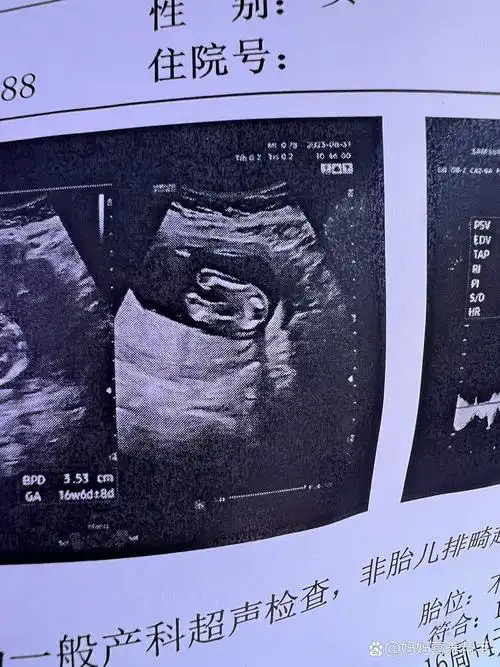

16周的b超图

孕16周时b超发现胎儿腹裂,羊穿结果显示正常,医生却说不容乐观